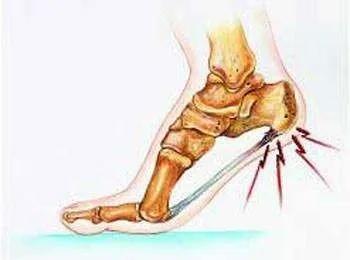

足跟是跟腱与跖筋膜的中转驿站,也是小腿向足部力学传导的枢纽(图2),足底跖腱膜是足底维持正常足弓、缓冲震荡、加强弹跳力作用的腱性组织。一般成人行走每天8000到10000步,而长期、慢性、轻微的累积伤,如果无法得到完全修复,就会造成足跟部腱骨连接部的慢性炎症,可以引起足跟部的疼痛,实质上就是足部跖筋膜纤维的断裂和其修复的反复过程(图3)。长时间的行走、过度的负重,会引起跖腱膜的劳损,导致局部无菌性炎症(图3),从而出现疼痛症状。后期,在足跟下方偏跖筋膜侧可有骨质增生,形成俗称的“骨刺”(图4,圈内)。

▲ 图2.足跟是跟腱与跖筋膜的力学传导枢纽

▲ 图3.足底跖筋膜炎

后者常被认为是足跟痛的原因,但临床观察显示它与足跟痛的关系并不恒定,跖筋膜炎不一定都伴有骨刺,有跟骨骨刺的人也不一定都有足跟痛。跖筋膜炎引起的足跟痛可以自然治愈。垫高足跟,减轻跟腱对跟骨的拉力,前足跖屈,缓解跖筋膜的张力,都可使症状减轻。